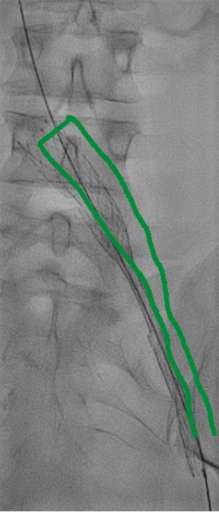

בתמונה 3 ו- 4:

- בכחול מסומן בלון מנופח בלחץ גבוה לפתיחת ההיצרות, ישנה נקודה בווריד עם היצרות קריטית שהיה קשה לפתוח באמצעות הבלון.

- בירוק מסומן תומכן (סטנט) שנפרס אך לא נפתח באופן אופטימלי לאור ההיצרות הקשה.